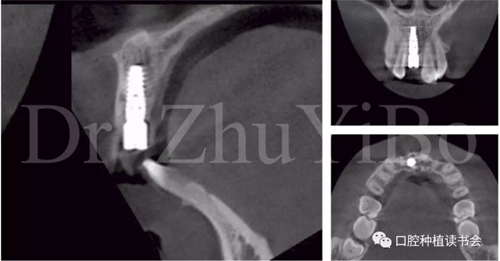

術(shù)前cbct顯示:右上中切牙牙根牙槽突類(lèi)型為一型(圖8)。牙齦為厚型牙齦類(lèi)型;咬合關(guān)系基本正常。

圖8 CBCT:11可見(jiàn)明顯根折線(xiàn),無(wú)法保留

圖15術(shù)后即刻CBCT示:種植體軸向及深度良好